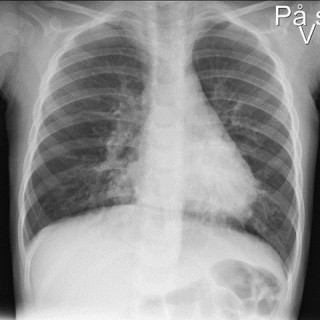

Denne kasuistikken beskriver alvorlig iatrogen botulisme etter behandling med injeksjon av botulinumtoksin ved en privatklinikk i utlandet. En kvinne i 40-årene ble akuttinnlagt i medisinsk avdeling grunnet økende svelgparese, svakhet i nakkemuskulatur, obstipasjon, munntørrhet, hodepine, fatigue, tunge øyelokk og uklart syn de siste fem dager. De siste tre dagene før innleggelsen hadde hun ikke fått i seg flytende eller fast føde, og hodet måtte støttes når hun skulle sette seg opp. Det fremkom at hun 15 dager tidligere hadde fått injisert botulinumtoksin type A mot migreneplager under et...